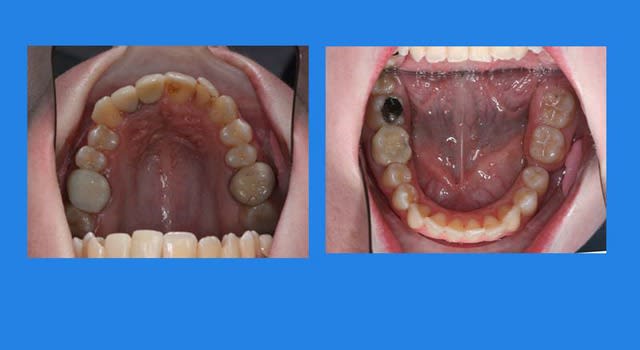

Voici le cas il y a 8 jours, c.a.d. 1 an et 1 mois après les photos de son dernier rendez vous

entre temps, elle est allée se faire faire des provisoires sur 12/11 par un confrère plus prés de son domicile

voici le résultat de l’absence de contention, qui aurait été (a mon avis) une erreur compte tenu que le cas n’était pas terminé

c’est mal foutu, c’est déglingué mais je n’ai aucune malposition Inc. Inf.

c.a.d. : AUCUNE RECIDIVE D’ENCOMBREMENT AVEC ROTATIONS

les dents ne sont pas alignées, mais j’ai mon espace globale, je peux poursuivre ce traitement avec sérénité